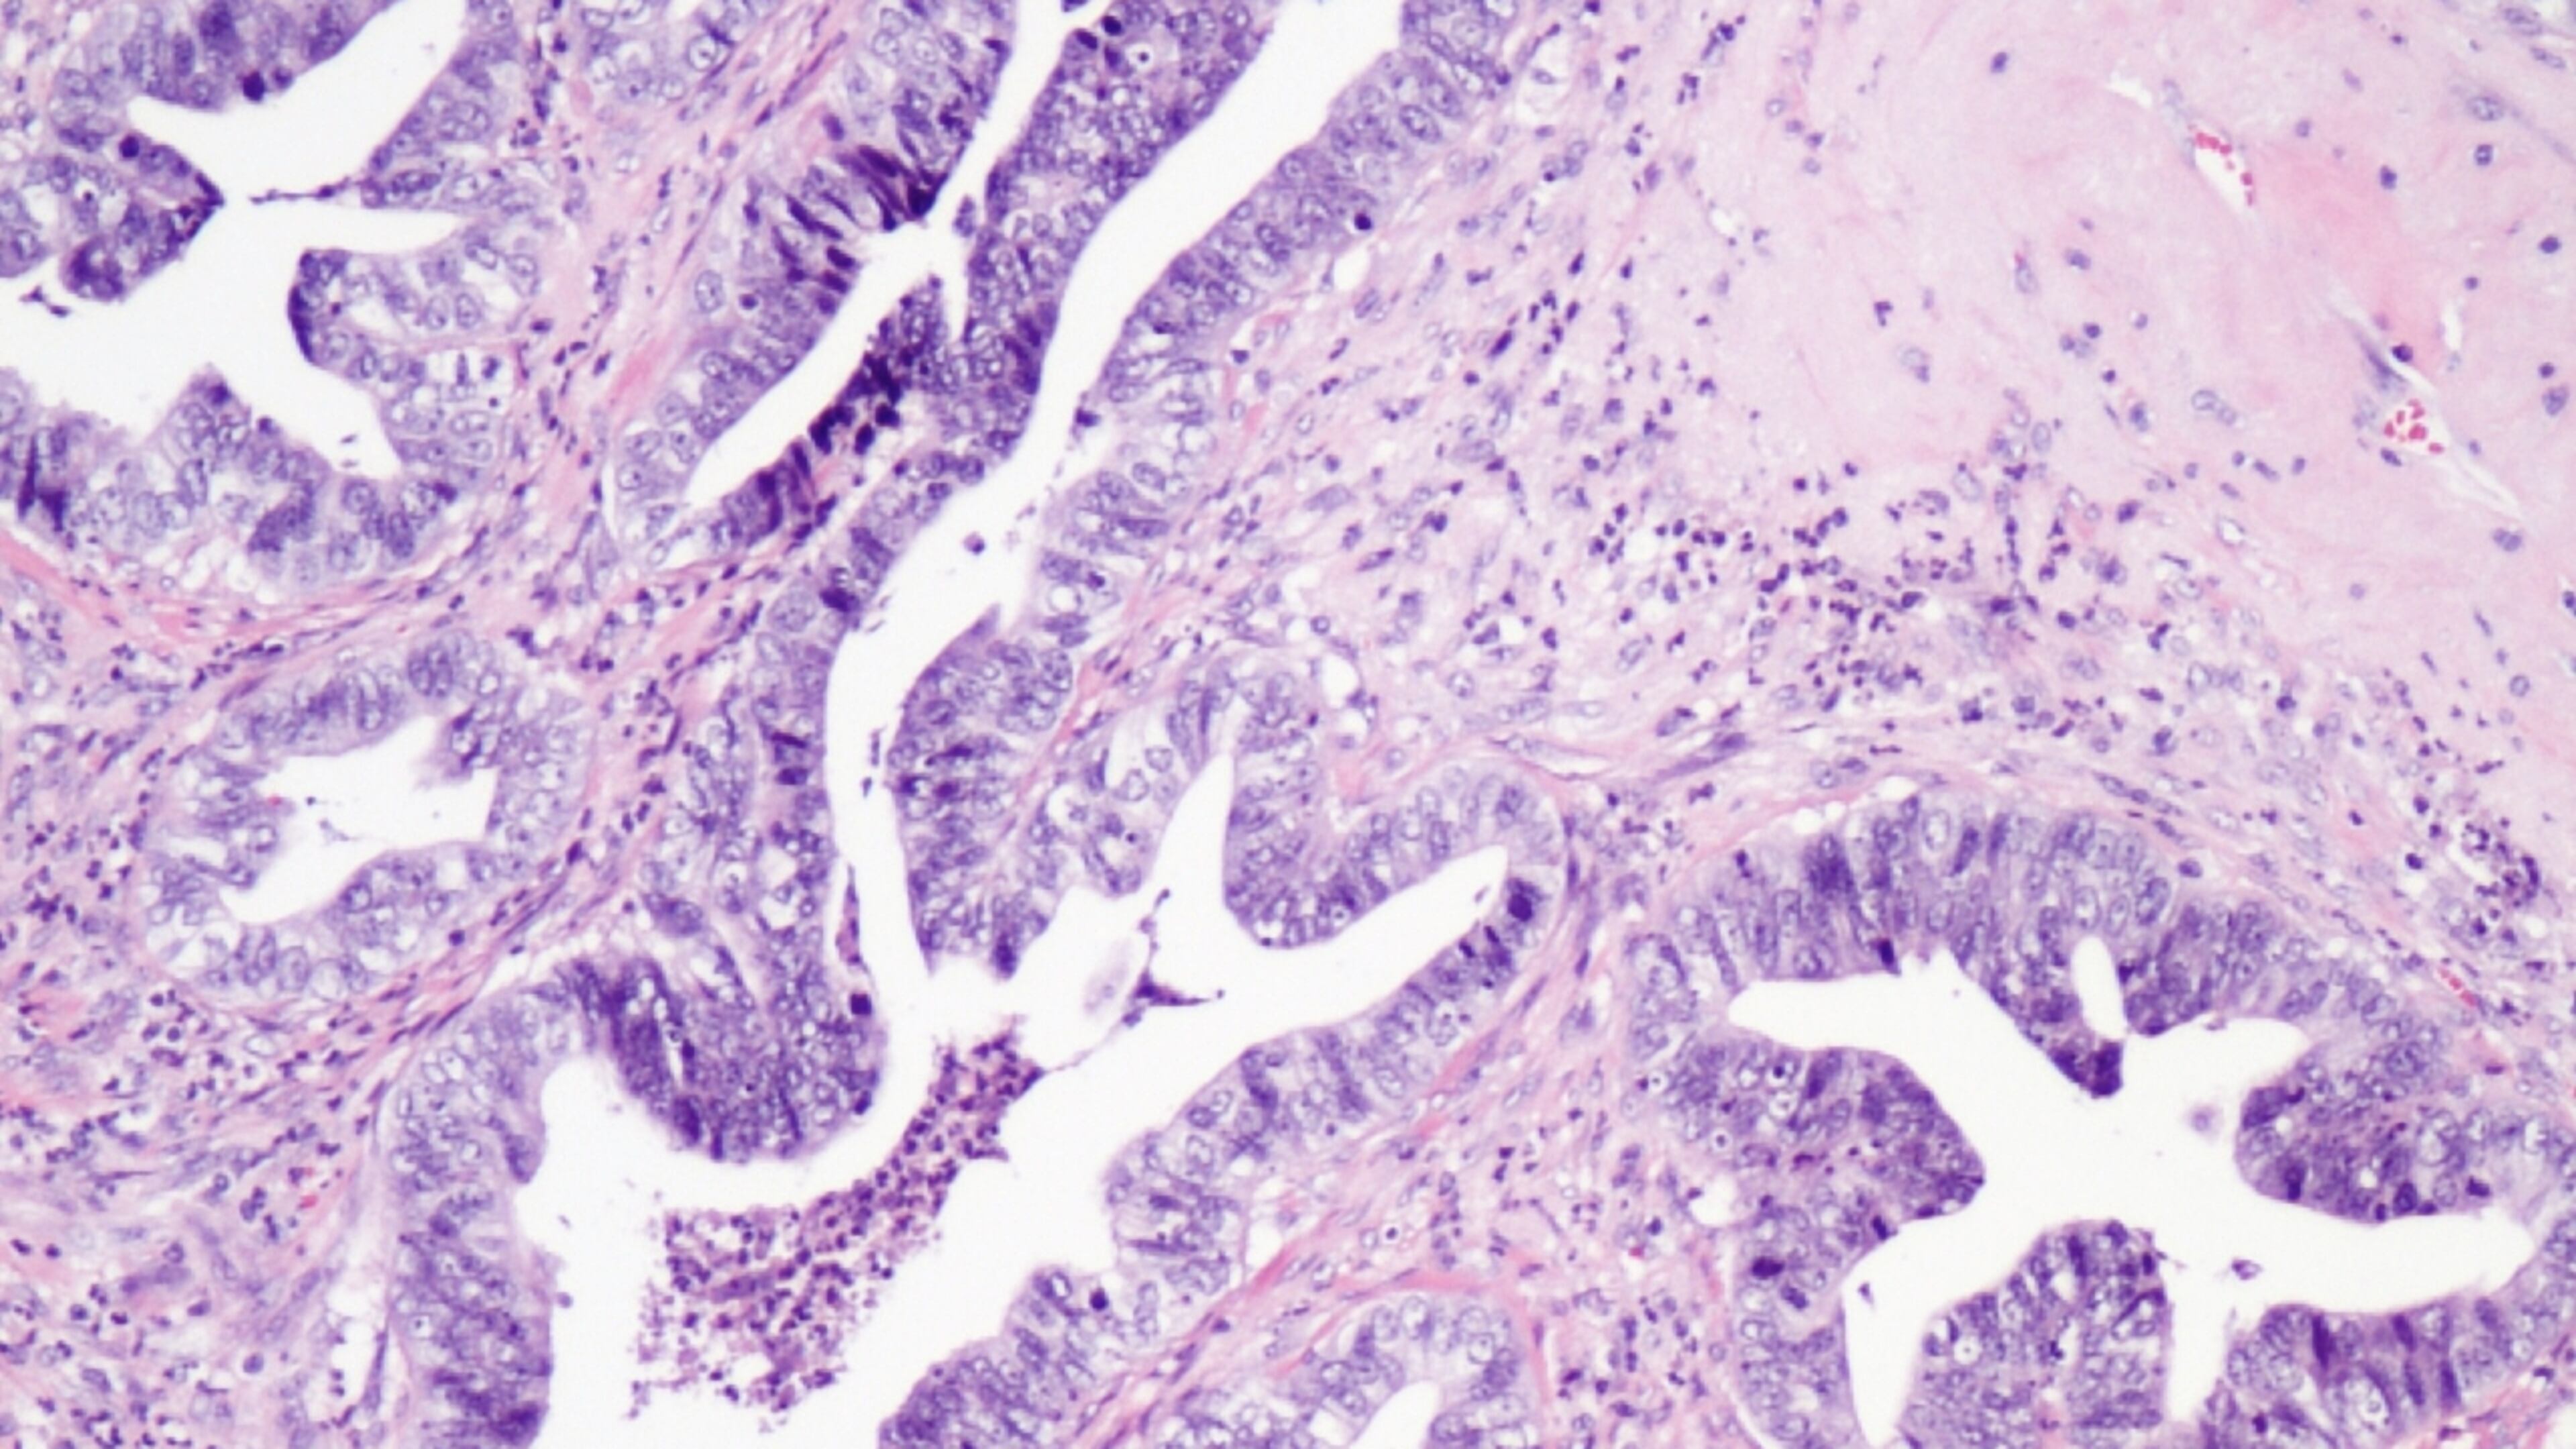

Cervical cancer is caused, in most cases, by the virus called human papillomavirus, or HPV. It can be transmitted through sexual contact. There is a vaccine for women age 26 and younger.